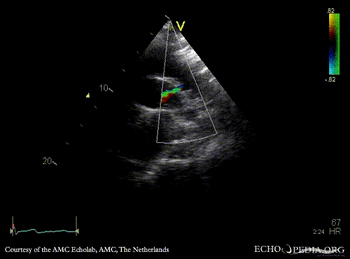

E00645.gif E00646.gif

Suprasternal view Suprasternal view with Color Doppler, open ductus Botalli

E00647.gif

Suprasternal view with Color Doppler, open ductus Botalli, zoom